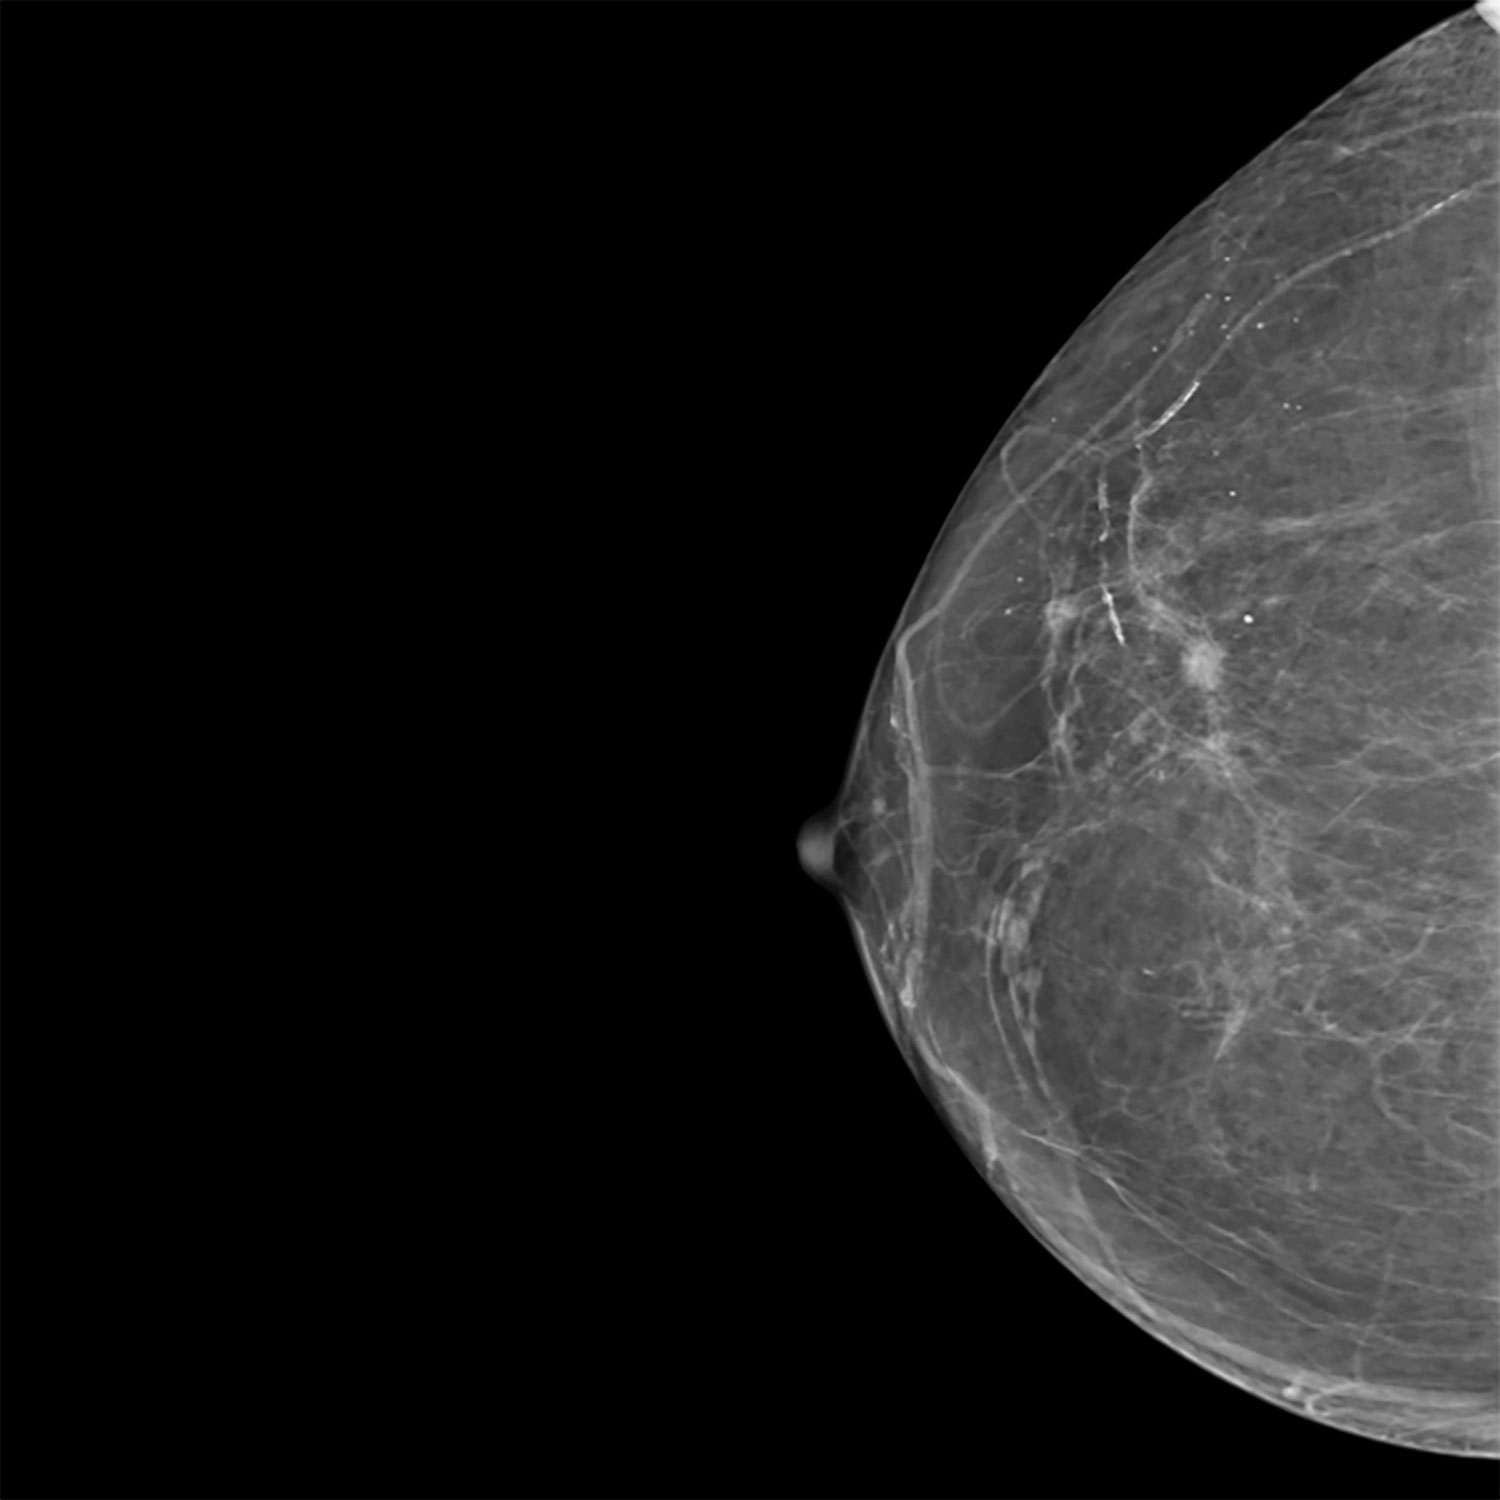

La mammographie est une imagerie radiologique utilisant des rayons X à faible dose, étant optimisée par les technologies les plus récentes, pour analyser la structure interne du sein.

L’examen permet d’identifier et de caractériser des lésions bénignes ou suspectes.

Il peut être complété par une tomosynthèse, acquisition 3D améliorant la détection et la localisation des anomalies, ainsi que par une échographie ou une biopsie si nécessaire.

L’acquisition de base comprend deux incidences par sein (face et oblique).